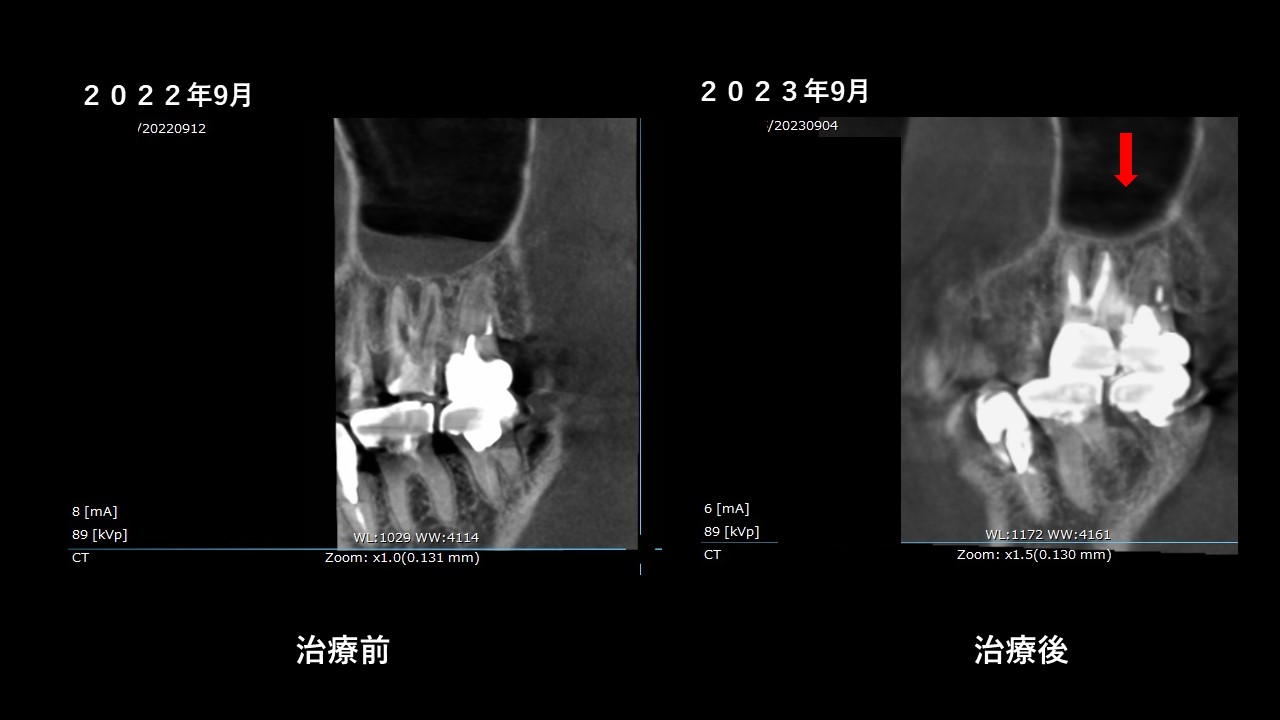

治療前と後の術前術後を比較してみましょう。

左上に撮影日の表示がありますが、

昨年2022年9月と、今年2023年9月のCT撮影です。

横側からの見た状態と、

正面からの状態。

矢印の場所の上顎洞の炎症が無くなり、本来の全体的に黒い空洞に戻っています。

治っていますね。

治療後のレントゲン写真では、根管にMTAセメントで充填してあり、

CTでは根の先まで白い詰め物がされているのが分かります。